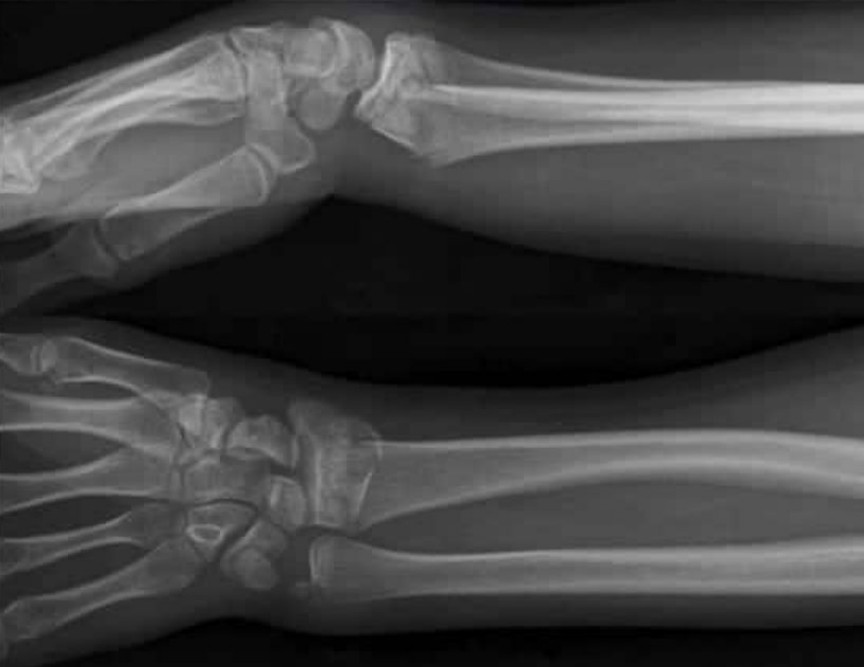

Wrist injury

A 38-year-old man presents with a painful left wrist after a fall on an outstretched hand. X-rays are provided.